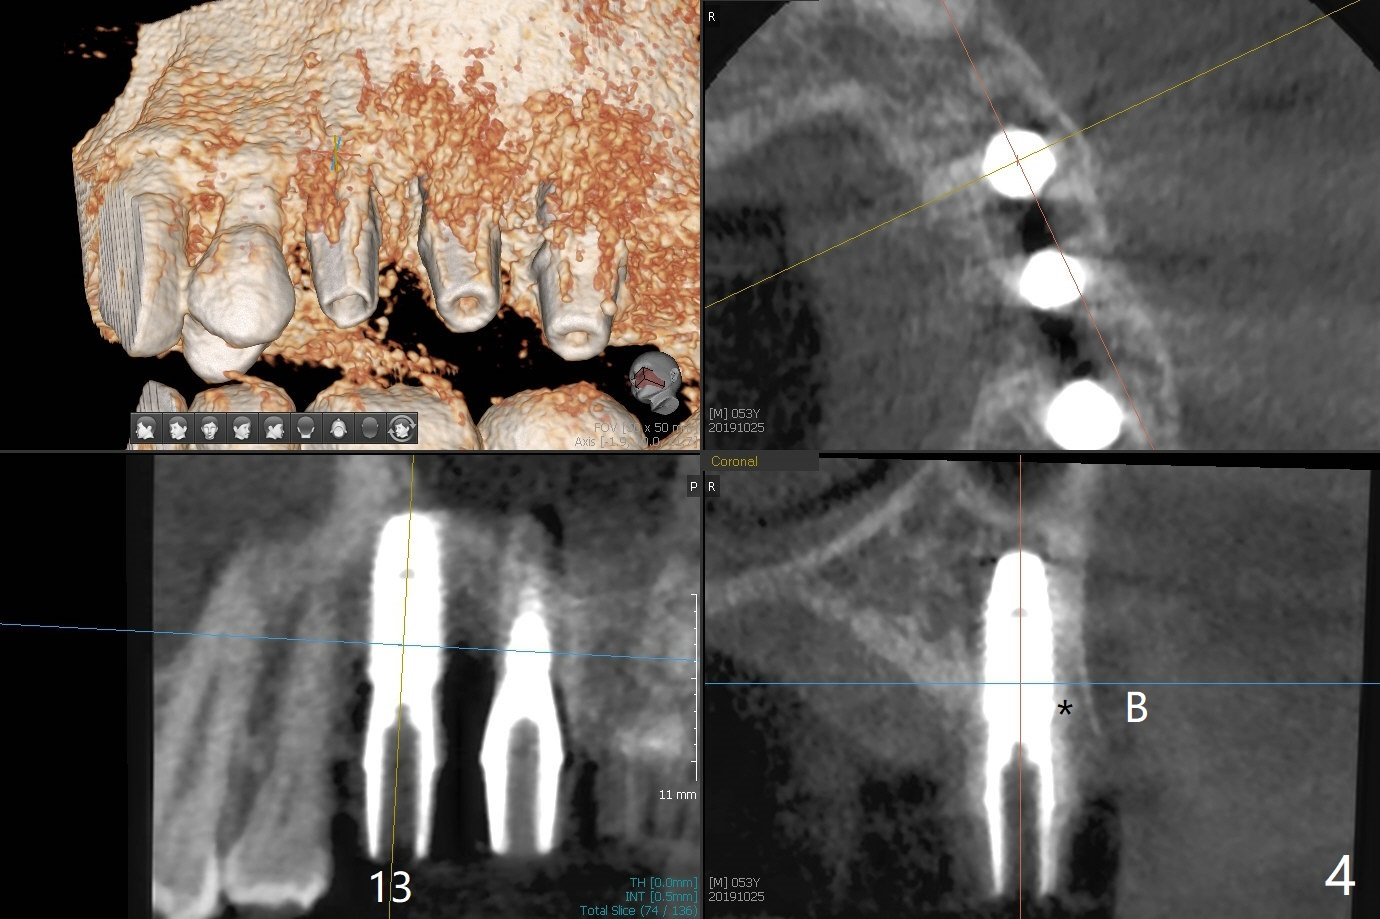

Extraction of abutment teeth associated with the loose FPD is not as easy as expected. Bony anchor placed at #14 (Fig.1 B) becomes loose while initial osteotomy a 2.2 mm drill at #13 for trajectory confirmation. The sinus membrane perforates at #15 when the sinus probe is being used. Luckily the perforation appears to be repaired with 2 pieces of PRF; sinus lift is assisted with a 4.5x10 mm dummy implant (Fig.2 *). Sinus lift at #14 is difficult and incomplete because of small osteotomy (Fig.3,5). In fact there is no sinus infection postop. Splinted immediate provisional is fabricated, but should be sectioned for individual units to form gingival scallops with distinct papillae. Three months postop, the splinted provisional is removed. The abutment at #14 is supragingival and is changed to 4.5x7(3) mm one. Individual temporary crowns are fabricated. Two weeks later, a small papilla forms between #14 and 15, while the temp at #13 is lost. The abutment at #13 changes to 4.5x7(5) mm one (Fig.7) with a new provisional, whereas those at #14 and 15 relined. In fact the abutment at #15 is incompletely seated (<) probably related to contact with the mesial crest (*). An abutment with smaller diameter and longer cuff at #15 seems to be completely seated (Fig.8,9, as compared to Fig.7). Following screw torque at 30 Ncm, impression is taken.